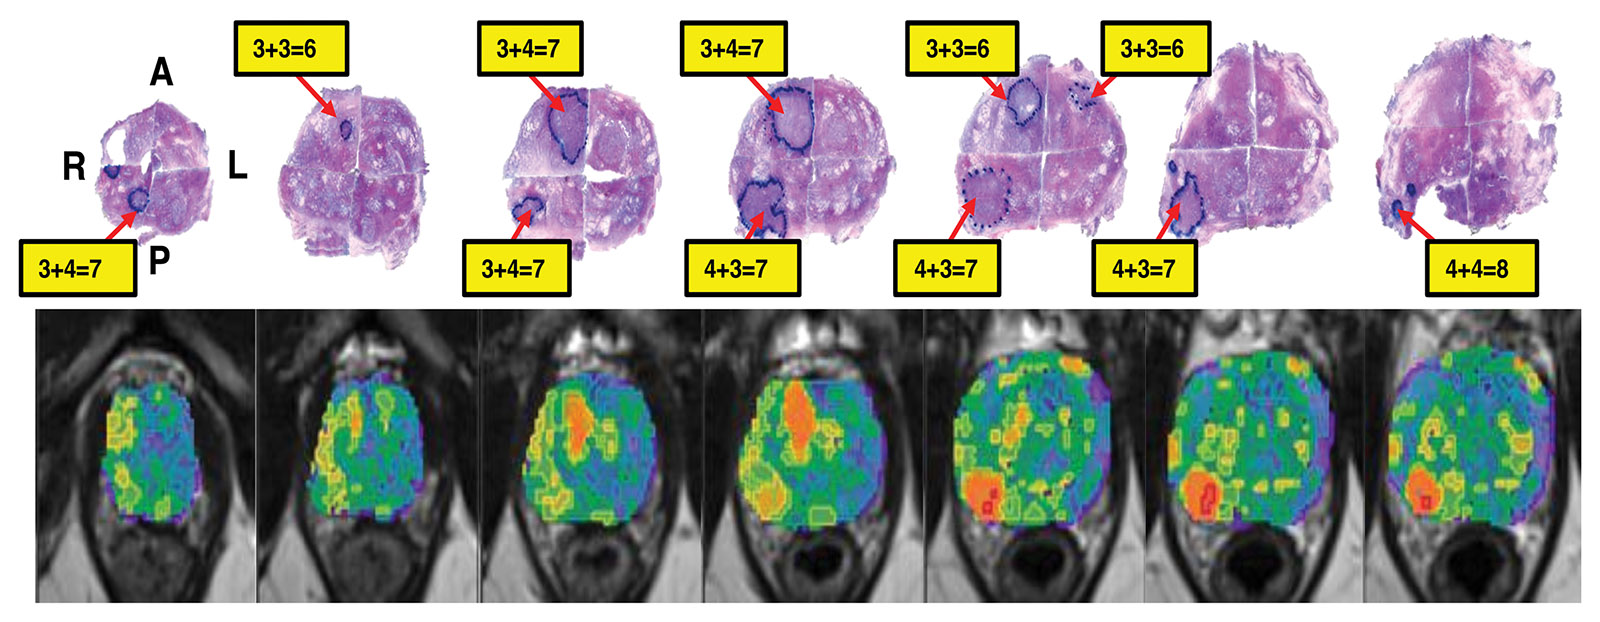

Correlation of habitat risk score in MRI images (bottom row) with the radical prostatectomy surgical specimens histological images (top row) in a man with prostate cancer.